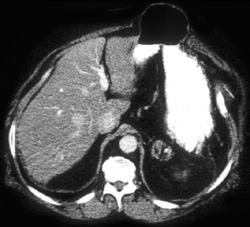

Linitis Plastica and Carcinomatosis